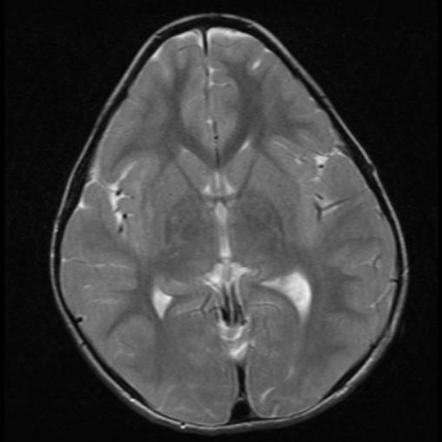

Epidermoid: purely neuroectoder, fluid-like content, T2 complex bright, T1 hypointense, homogenenous/poor enhancement of capsule, and restricted diffusion. 20-40 yearsof age behind ears. Dermoid: Neuroectoderm+glands, lipidic-like content, T2 bright, T1 hyperintense, calcification of capsule, enhancement of capsule. Earlier presentation and midline. Nasal dermoid cysts may be associated with a sinus tract that extends for variable distances in the prenasal space to the foramen cecum. Nasal dermoid and epidermoid cysts are typically surgically resected due to the potential for an intracranial connection and the risk of CNS infection, as well as for cosmetic reasons IMAGE 1 Epidermoid IMAGE 2: Nasal dermoid